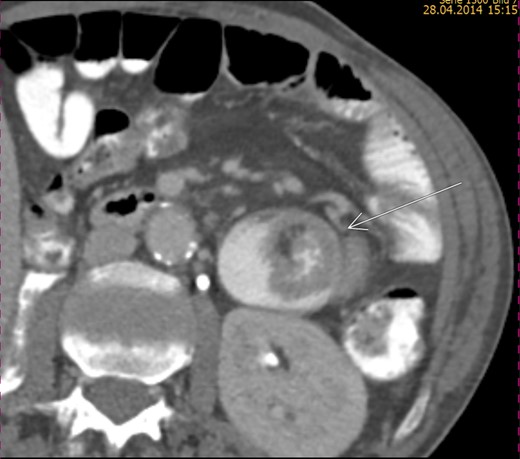

A 61-year-old man with metastatic clear-cell RCC diagnosed 3 years previously presented to the local accident and emergency department (A&E) because of abdominal pain and vomiting. After tumour nephrectomy, he received sequential treatment with sunitinib, everolimus, axitinib and sorafenib for lymph node and lung metastases. Sorafenib was stopped 1 month before admission, when the patient developed dyspnoea as a result of severe normochromic/normocytic anaemia and compression of the right main bronchus by a right hilar, lymph node metastasis. At that time, CT showed no other sites of progressive disease. As the patient reported intermittent melaena, oesophago-gastroduodenoscopy and colonoscopy were performed. No evidence of tumour or bleeding was evident. Thus, anaemia was attributed to progressive carcinoma and sorafenib treatment. Over the course of 4 weeks, the patient was treated with palliative radiotherapy to the right pulmonary hilum and received frequent erythrocyte transfusions for refractory anaemia. At presentation to A&E, he had had recurrent abdominal pain and emesis for 1 week. The physical examination was unremarkable. An abdominal CT scan revealed small bowel obstruction and triple jejuno-jejunal intussusception with the typical ‘target sign’, as well as several apparently intra-luminal tumour masses (Fig. 1), which had not been evident on the CT scan 6 weeks earlier. No tumour progression in other metastatic sites was detected.

CT scan revealing enhanced masses and jejunal invagination (target sign).